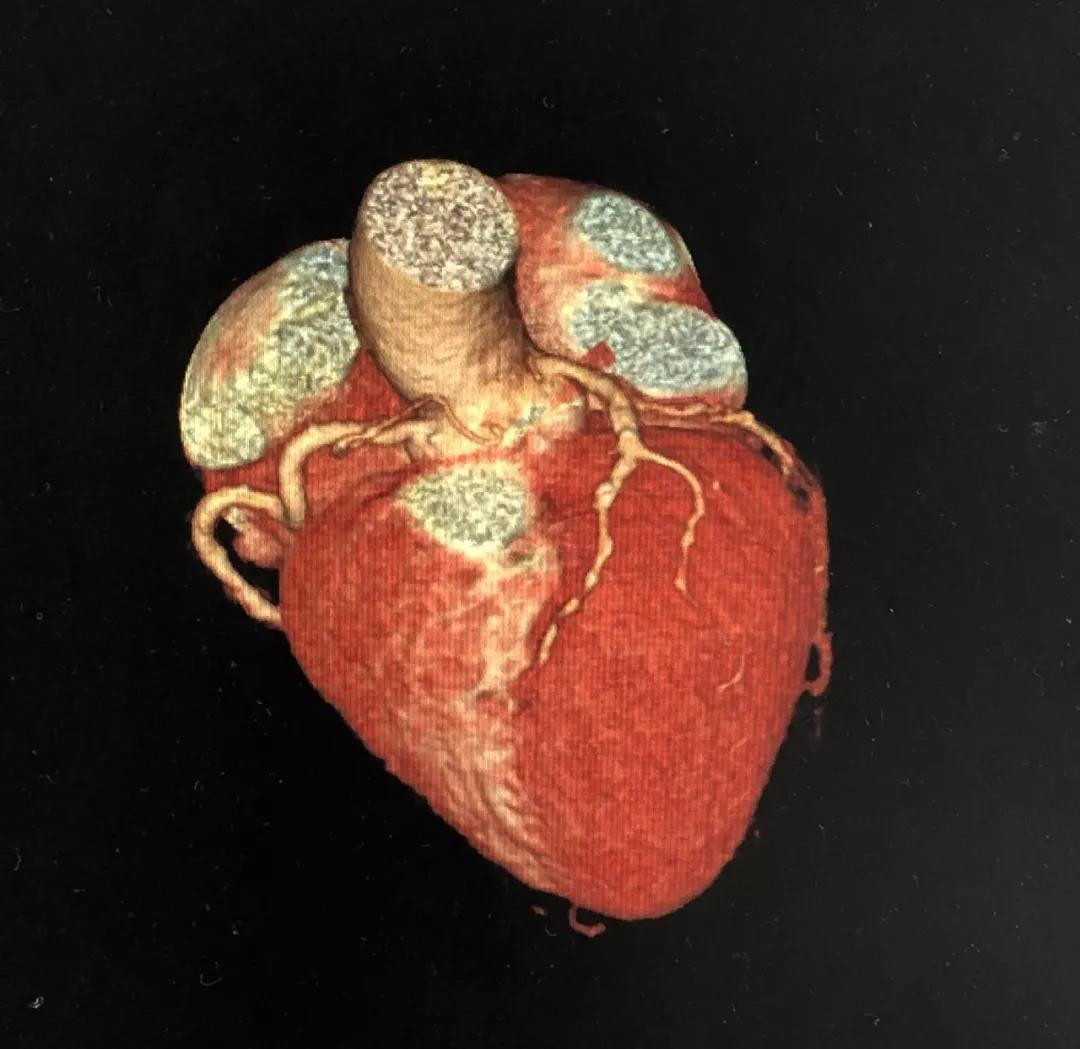

冠状动脉CTA

CCTA LAD病变特点:

近段血管较直

中远段血管偏细

中远段血管病变弥漫

病变段扭曲不很明显

病变段无重要分支发出

病变血管段有局灶点状钙化

CCTA LCX病变特点:

LM前分叉正常

LCX相对较直

中段病变伴局灶点状钙化